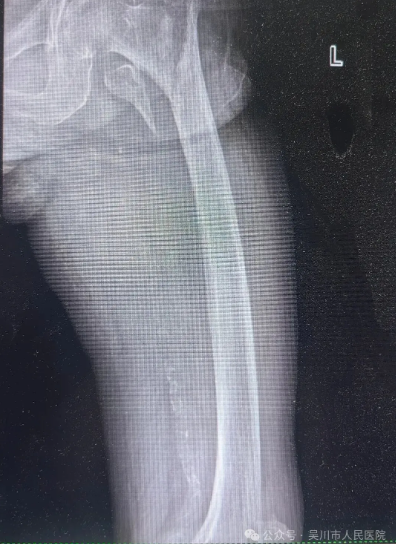

了解患者的情况后,我院骨外科三区主任、主任医师曾维,主治医师宁健文和护士长刘春莲带领医护团队第一时间为李某完善相关检查,明确诊断为 “左股骨粗隆间骨折”,并结合患者的年龄、身体状况制定了个性化的治疗方案。11月21日,该科手术团队凭借精湛的医术,顺利为李某实施 “左股骨粗隆间骨折切开复位髓内针内固定术”。在术后恢复期间,医护团队更是给予了李某全方位的细致照护,让远在他乡的李某感受到我院医护人员如同家人般的关怀与温暖。

术前/术后对比